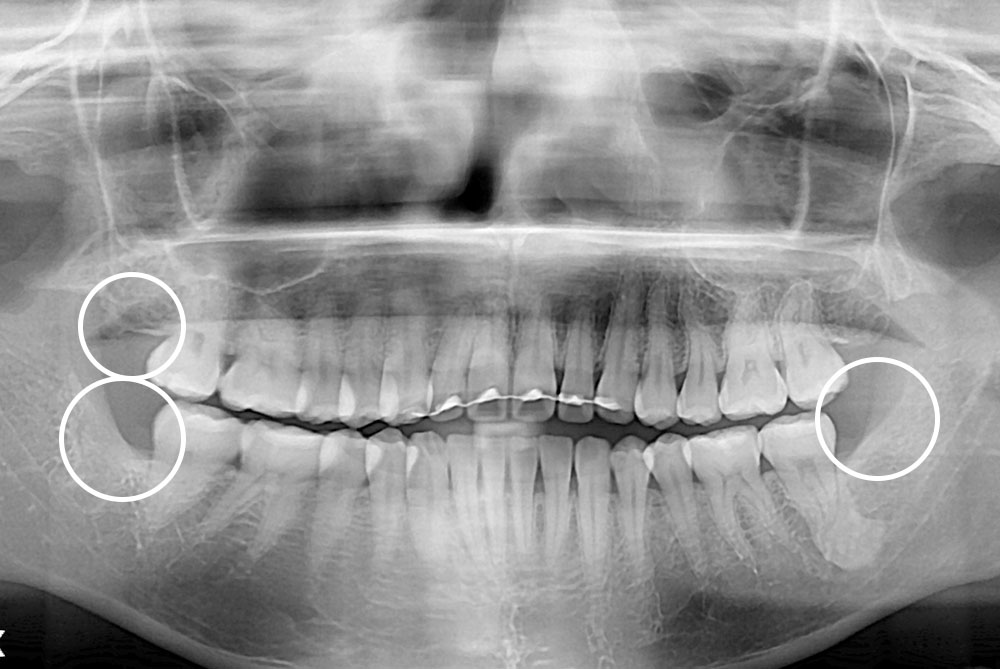

[사랑니] 매복 사랑니 발치

치료전 : 2017-08-03